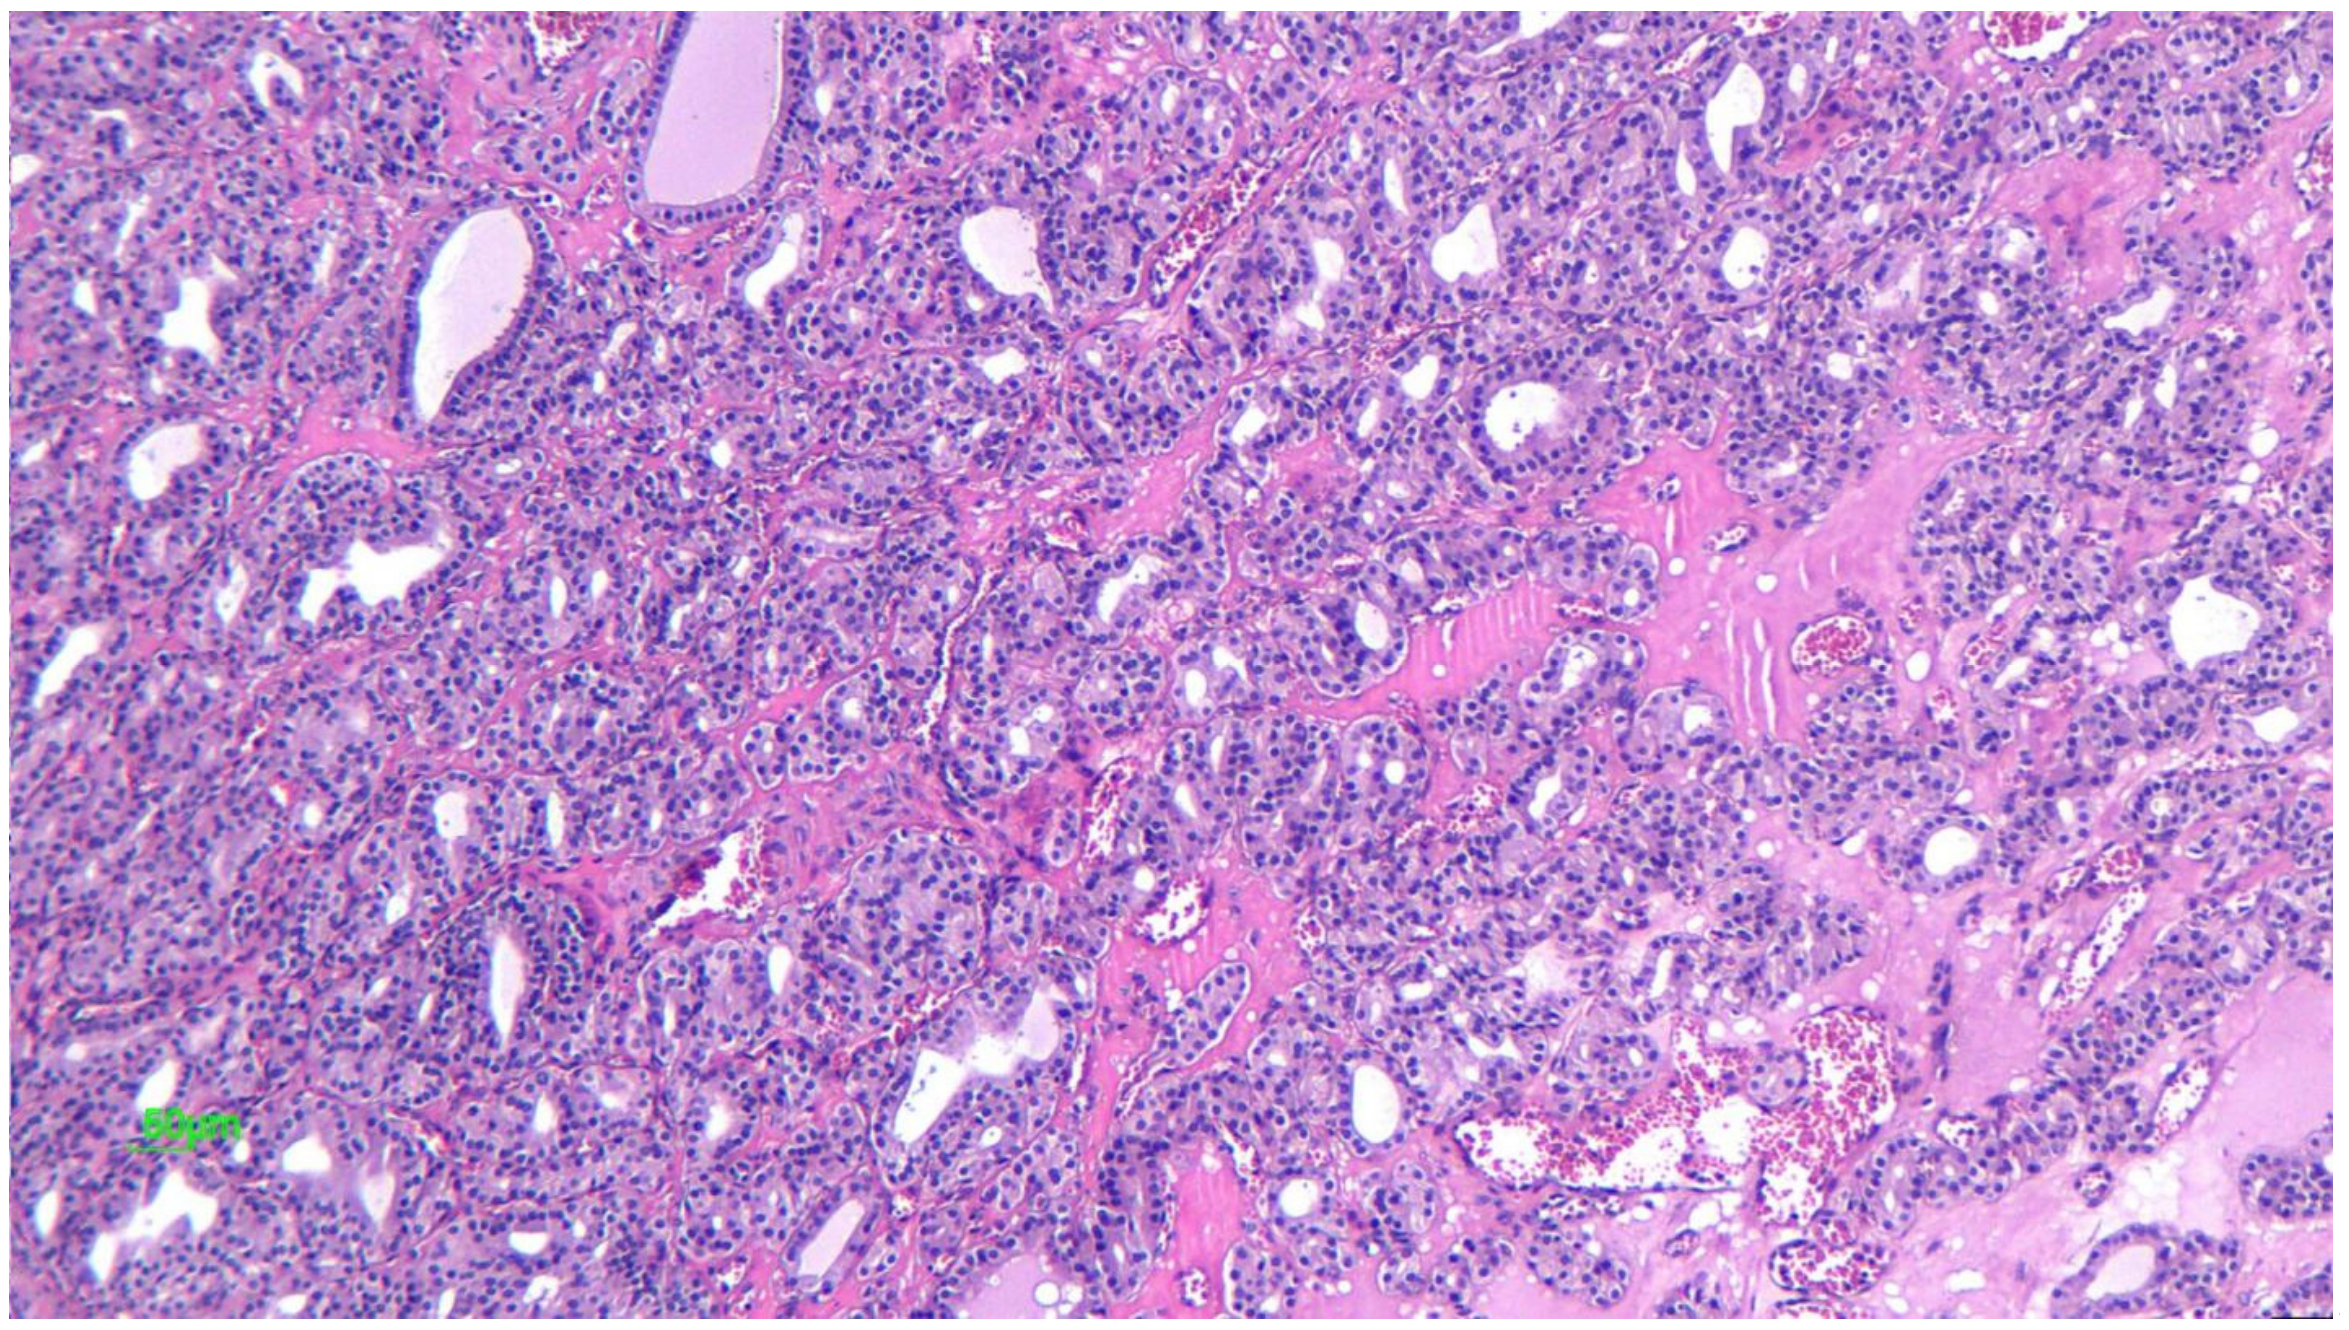

2.2.3. Microscopic Features

2.4.2. Microscopic Features

2.7.2. Microscopic Features